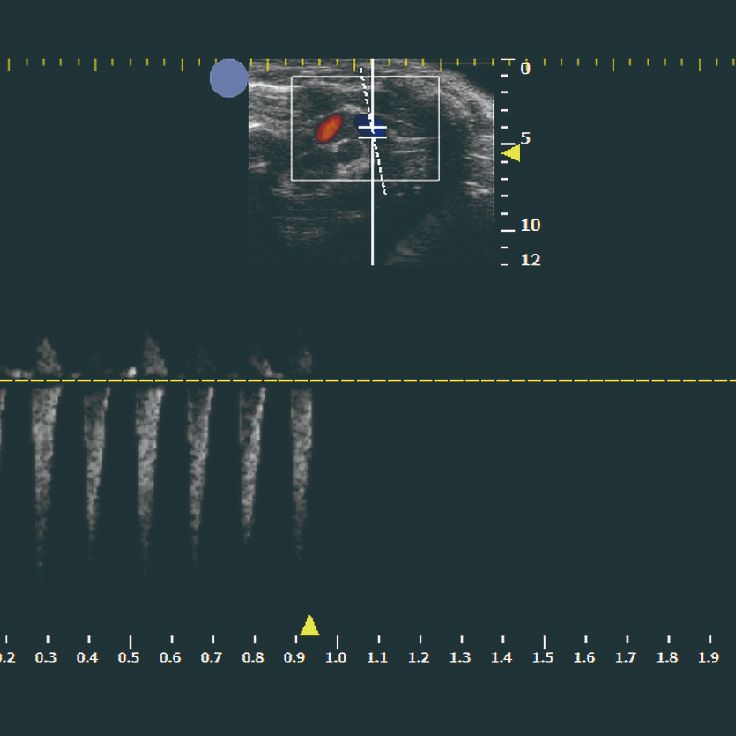

| 兔子 | 450元/样/次 | 包含B超截图+视频+心脏/血管参数分析 | 心脏、主动脉、原位肿瘤测量等 |

| 大小鼠 | 350元/样/次 | 单纯B超截图/视频 |

小动物B超

¥350 - 450